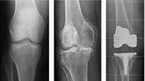

서울 송파구에 사는 75세 A 할머니는 최근 무릎이 붓고 아파서 괴로운 날이 많아졌다. 친구들과 외출을 다니는 것도 힘들고, 귀여운 손주들과 같이 노는 것도 부담스럽기만 하다. 지병인 고혈압, 당뇨 때문에 규칙적인 운동을 하는 것이 중요하지만 무릎이 아파서 제대